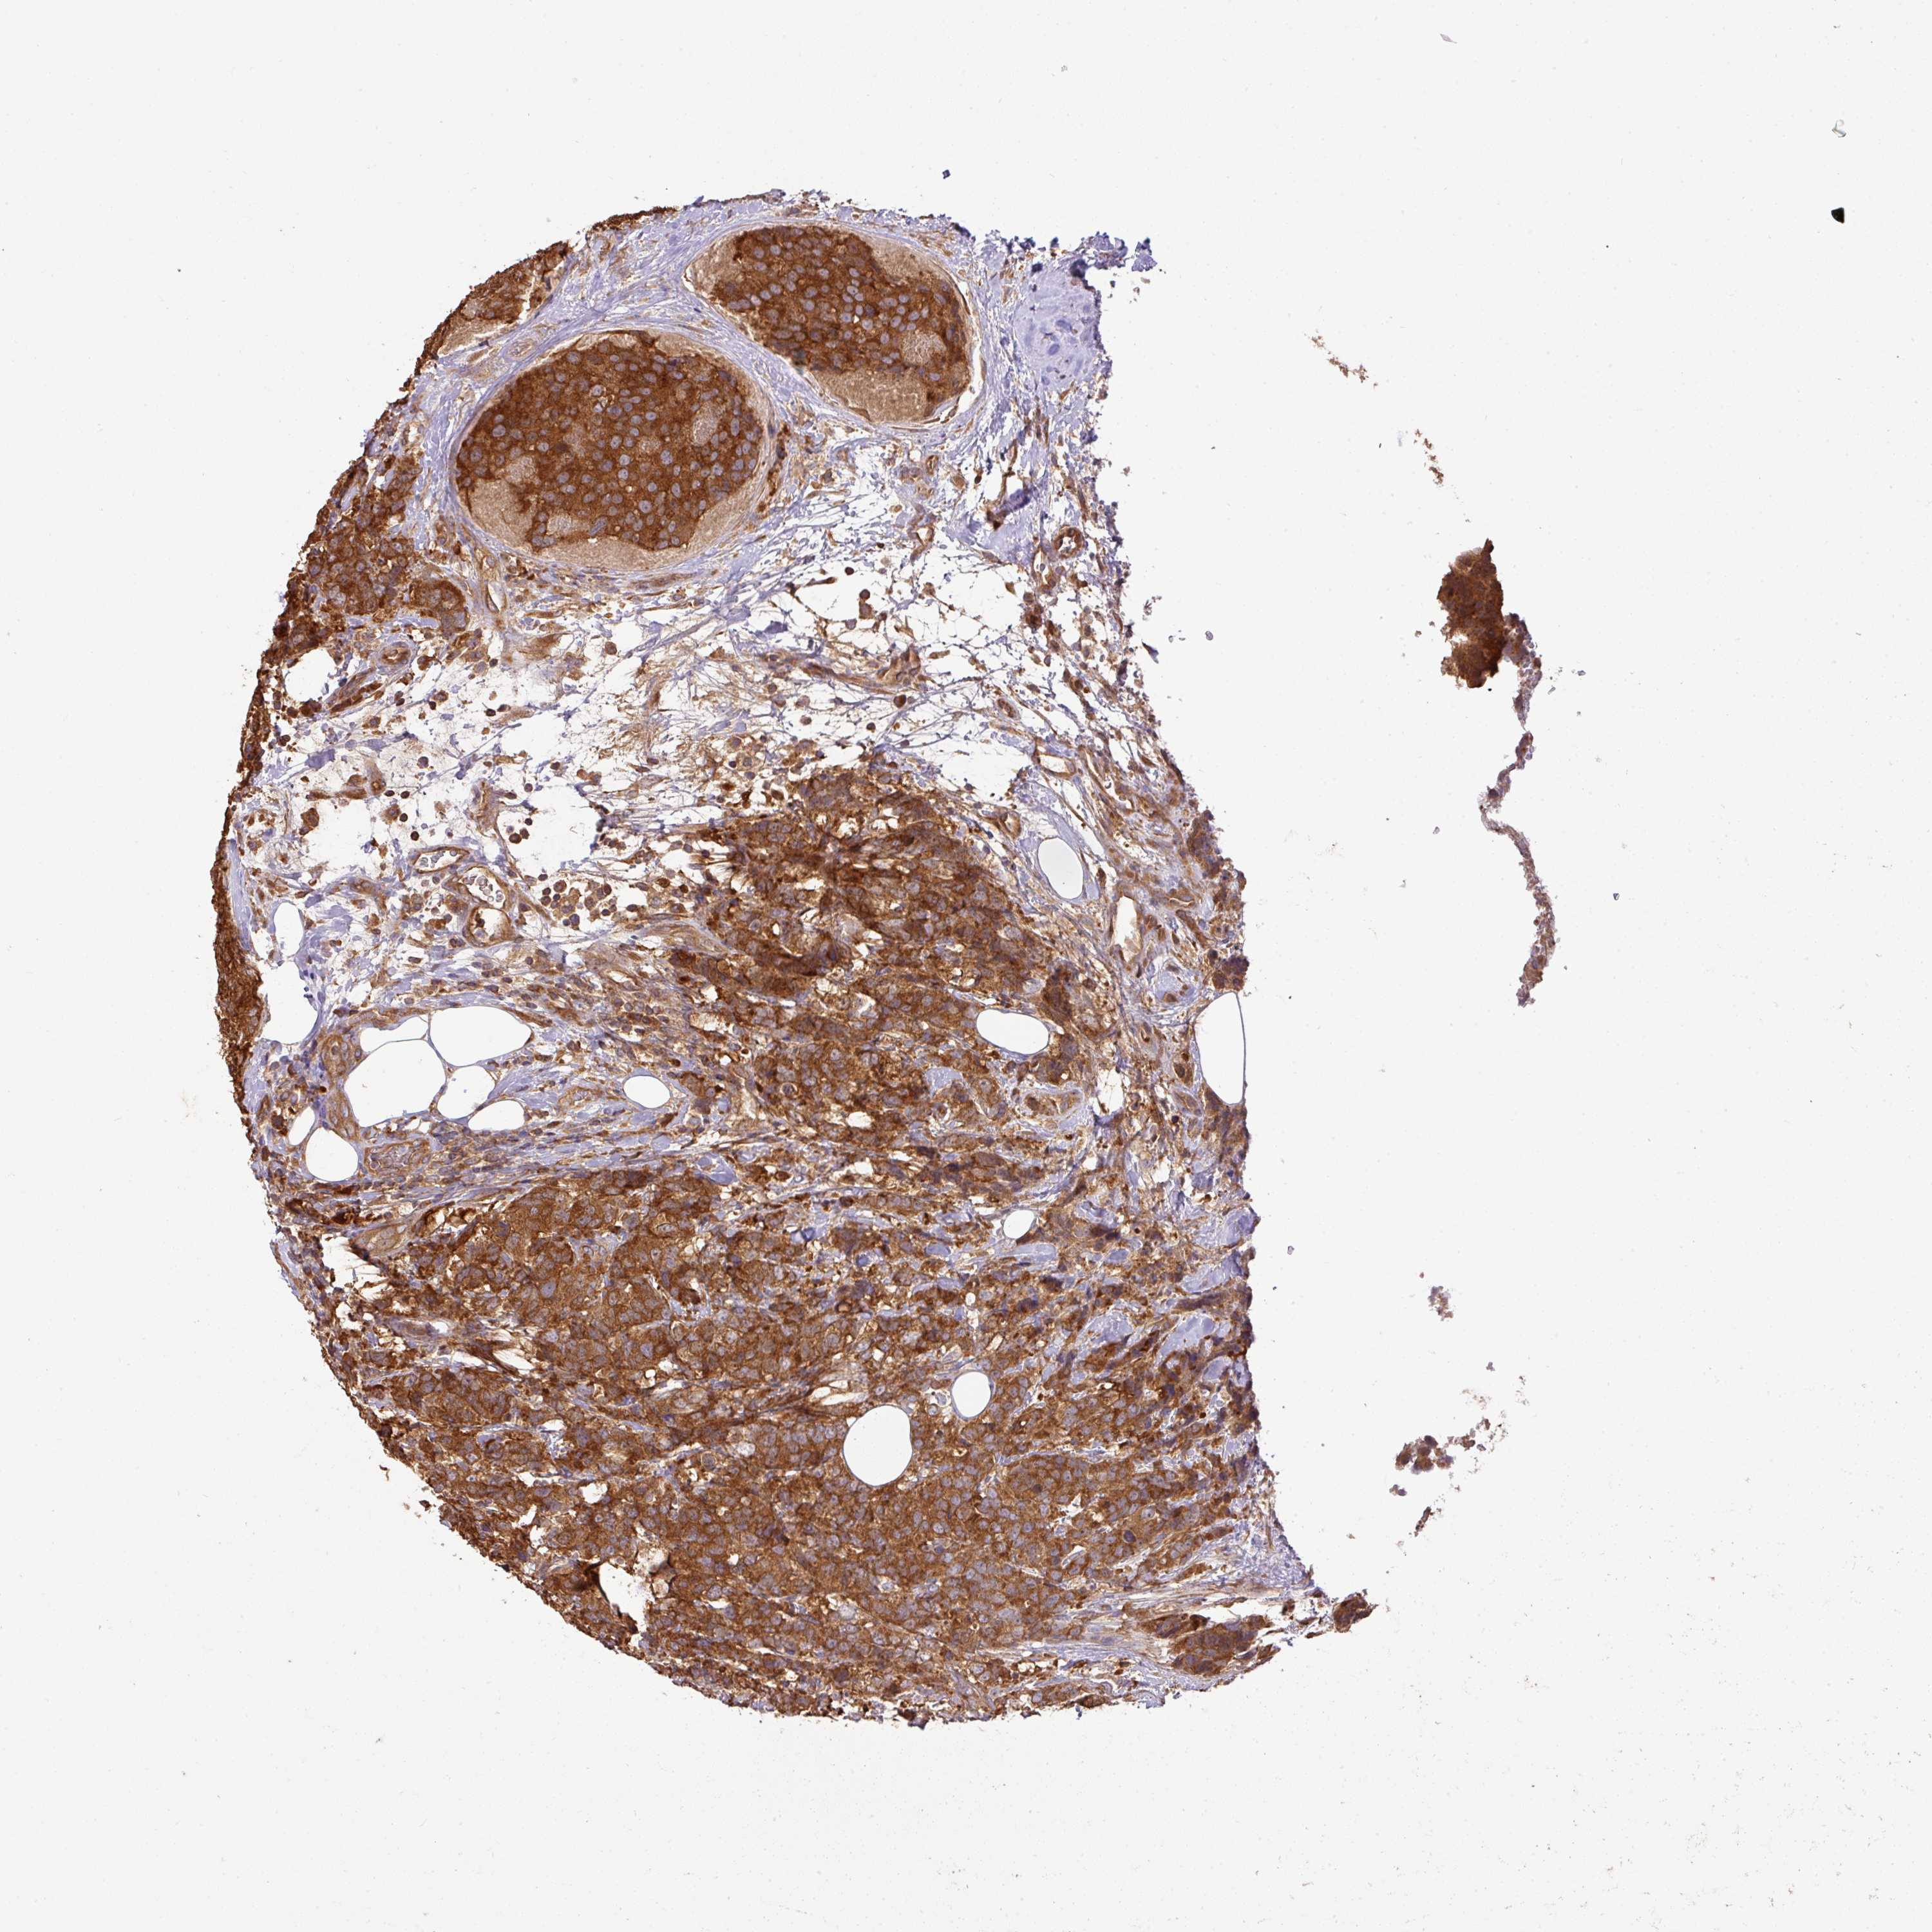

CANCER BREAST CANCER Show tissue menu

BRCA TCGA BRCA VALIDATION PROTEIN EXPRESSION